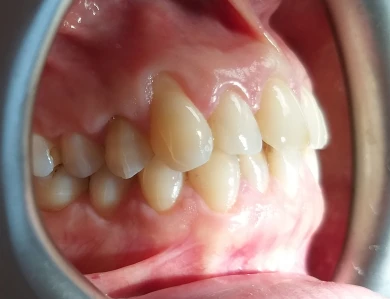

Improving Aesthetics After Orthodontic Treatment

Our patient had multiple discolored teeth and composite fillings placed many years ago. After successful […]